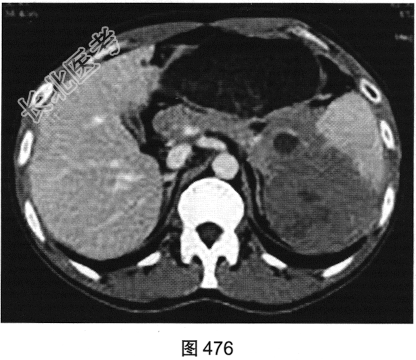

- 多项选择题3.[提示]患者行CT动态增强扫描,如图474~图476所示。对CT图像描述正确的是( )

A、脾血管被病灶侵犯

B、CT平扫呈不均匀低密度

C、胰腺被病灶侵犯

D、病灶门脉期轻度强化

E、病灶边界清晰,具有包膜

F、病灶动脉期无强化